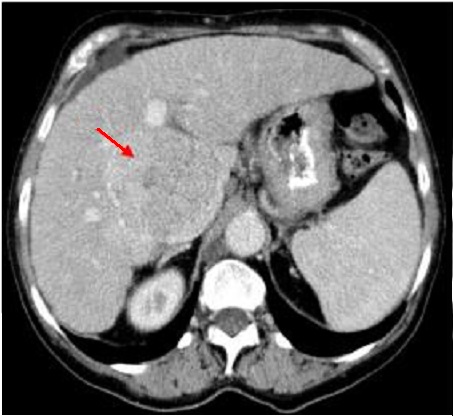

Mêm cas au temps arteriel :

Image de rehaussement du tumeur ( fleche rouge ) .

Aort abdominale et artere du tronc coeliaque en

voyait net . Adenophathie hilaire du foie est en

presence |